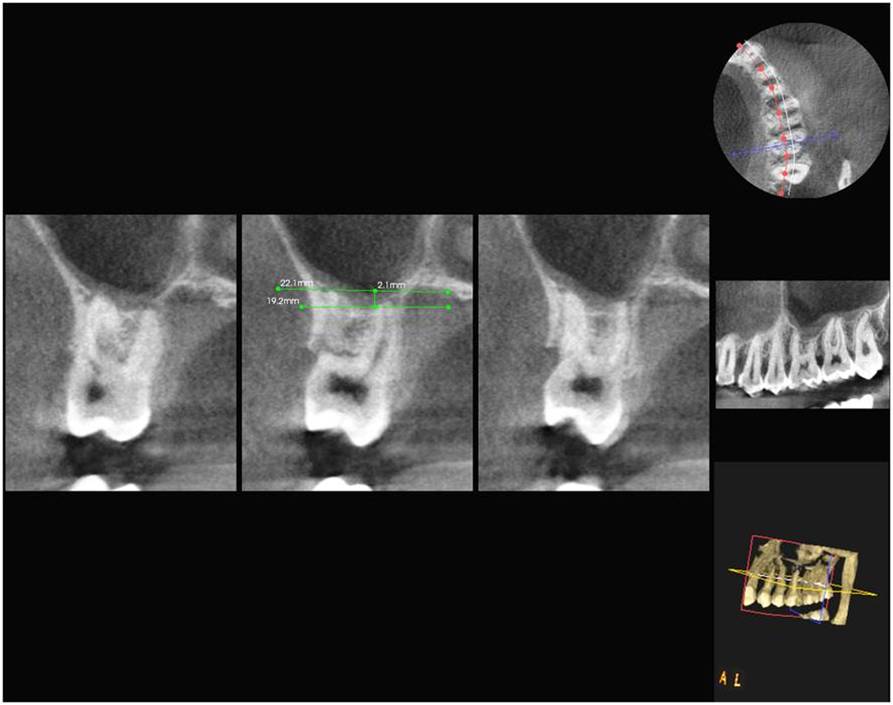

Materials and Methods: A total of 510 maxillary teeth from 85 patients were classified according to their topographic relationship to the maxillary sinus and measured according to their projection lengths on the sinus cavity using OPG and DVT modalities.

Results: In cases of classification 0, 85% and in classification 1 , 55.3% cases shows similar classification in both OPG and DVT. 28.5% of cases in both imaging modalities show classification 2. Only 15.9% of teeth roots exhibits classification 3. 11.1% of cases showed classification 4.The panoramic radiograph showed a statistically significant 2.24 times longer root projection on the sinus cavity in OPG comparison to DVT images.

Conclusion: Teeth roots projecting in to the sinus in OPG, shows no vertical protrusion in to the sinus in DVT images. Hence DVT was better than OPG with measurements that were more exact and closer to anatomical reality.